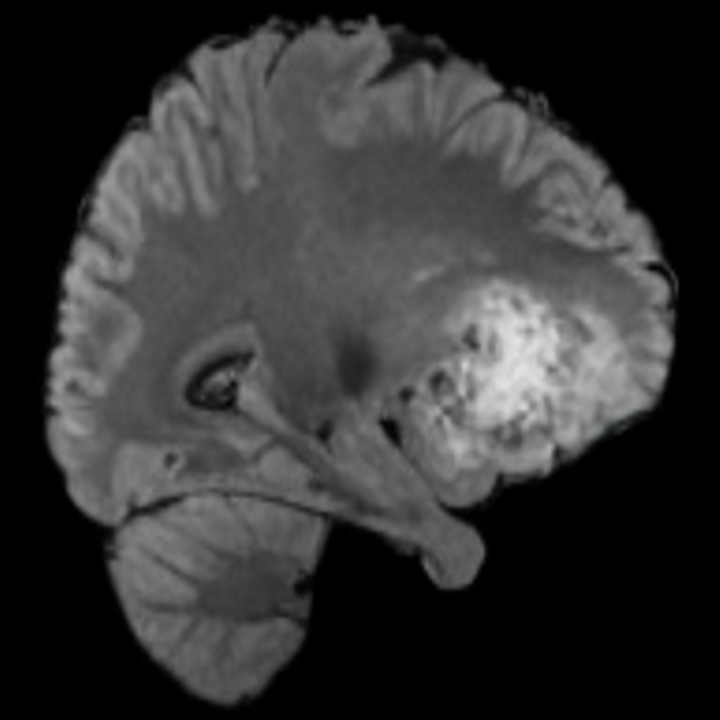

![]() |

|||

Tumour Information Preservation. For the brain tumor segmentation, we use a Swin UNETR model[28, 70], trained with random rotation, and intensity as data augmentation. On the test set with human ground-truth annotations (), the brain volumes generated from single slice input preserve the volume of the different tumour components (paired t-test, for all 3 classes). In Figure 4, we highlight the tumor profiles of the generated MRIs compared to the ground truth tumour profile. The real MRI Dice score in the test set is 85.15 while the generated MRIs from a single slice have a dice score of 83.09. This shows how the generated MRIs indeed preserve the tumor information and can act as an affordable and informative pseudo-MRI, before conducting an actual costly MRI examination in hospitals. More detailed results are provided in supplementary material.